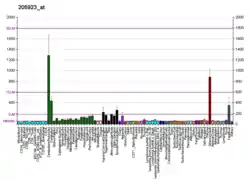

Fatemi et al. conducted the study in which RELN mRNA and reelin protein levels were measured in rat prefrontal cortex following a 21-day of intraperitoneal injections of the following drugs:[28]

| Reelin expression | Clozapine | Fluoxetine | Haloperidol | Lithium | Olanzapine | Valproic Acid |

|---|---|---|---|---|---|---|

| protein | ↓ | ↔ | ↓ | ↓ | ↑ | ↔ |

| mRNA | ↑ | ↑ | ↓ | ↑ | ↑ | ↓ |

In 2009, Fatemi et al. published the more detailed work on rats using the same medication. Here, cortical expression of several participants (VLDLR, DAB1, GSK3B) of the signaling chain was measured besides reelin itself, and also the expression of GAD65 and GAD67.[199]